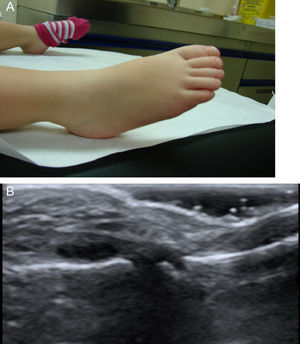

Artritis en pacientes con enfermedad de KawasakiÚnicamente en 7 de los 42 niños se recogió la presencia de clínica articular (16%). La forma oligoarticular fue la predominante (57%) afectando a miembros inferiores, rodillas y especialmente tobillos. La segunda en frecuencia fue la afectación monoarticular de cadera (29%) y el estudio ecográfico recogido en la historia mostró la presencia de distensión de la cápsula articular por derrame sin hipertrofia sinovial ni señal doppler asociada. Por último, solo un paciente presentó afectación poliarticular (14%), especialmente en tobillos, rodillas, manos e IFP del pie (fig. 1). La ecografía de grandes articulaciones demostró distensión capsular provocada por derrame sin hipertrofia sinovial ni señal doppler y acompañado de intensa afectación periarticular.